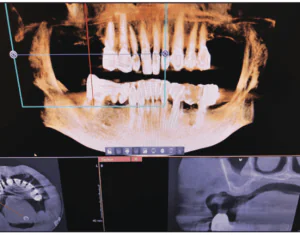

INTRODUCTION Reconstruction of edentulous areas with dental implants is a viable alternative to conventional dental procedures and has become rather mainstream within the profession and